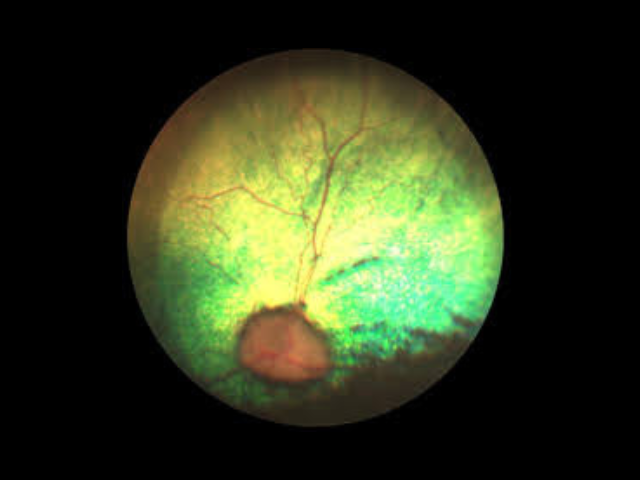

As leading veterinary ophthalmologists in Southern California, we specialize in advanced eye surgeries, cataract removal, glaucoma treatment, corneal repair, and retinal disorders. Our pet eye care specialists utilize state-of-the-art equipment and proven surgical techniques to preserve and restore vision in companion animals.